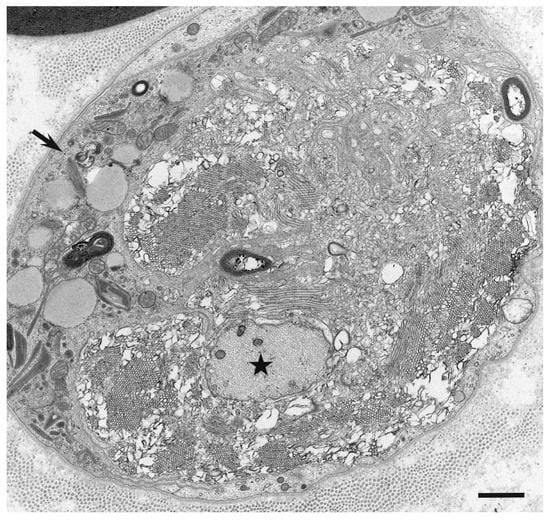

- Koike, H.; Nishi, R.; Ikeda, S.; Kawagashira, Y.; Iijima, M.; Katsuno, M.; Sobue, G. Ultrastructural mechanisms of macrophage-induced demyelination in CIDP. Neurology 2018, 91, 1051–1060. [Google Scholar] [CrossRef]

- Koike, H.; Fukami, Y.; Nishi, R.; Kawagashira, Y.; Iijima, M.; Katsuno, M.; Sobue, G. Ultrastructural mechanisms of macrophage-induced demyelination in Guillain-Barré syndrome. J. Neurol. Neurosurg. Psychiatry 2020, 91, 650–659. [Google Scholar] [CrossRef]

- Koike, H.; Katsuno, M.; Sobue, G. Deciphering the mechanism and spectrum of chronic inflammatory demyelinating polyneuropathy using morphology. Clin. Exp. Neuroimmunol. 2018, 9, 35–46. [Google Scholar] [CrossRef]

- Koike, H.; Katsuno, M. The role of macrophages in Guillain-Barré syndrome and chronic inflammatory demyelinating polyneuropathy. Neurol. Clin. Neurosci 2021, in press. [Google Scholar] [CrossRef]